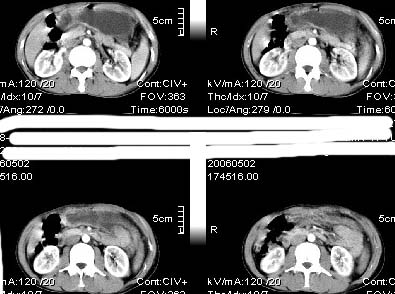

男:42岁。反复恶心呕吐半年。b超:右肝内多发占位,胆石胆囊炎.胆总管扩张

本例特点动脉期右叶近肝门区可见高密度强化,后段也见早期强化,静脉期肝门区高密度区造影剂退出,余密度均匀,考虑肝癌伴动静脉漏,肝右叶上段可见扩张胆管,考虑由于肿瘤压迫胆管引起阻塞,

鉴别 胆管细胞性肝癌,无动脉期强化,